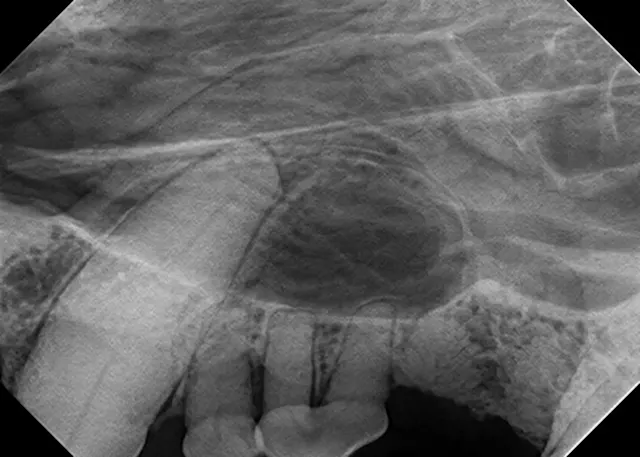

Bisecting Angle Technique

This technique, which is used to image the rostral mandible and entire maxilla, is the only technique that produces an image without distortion when done correctly. Some technicians find the bisecting angle technique difficult to grasp; however, it can be simplified with proper patient and equipment positioning.

For example, image the caudal cheek teeth in the maxilla with the tube head at a 60° angle from the horizon.2 When the patient is positioned with the maxilla parallel to the horizon, the sensor can also be placed parallel to the horizon (ie, inside the oral cavity and adjacent to the desired teeth), making it much easier to visualize the angle.